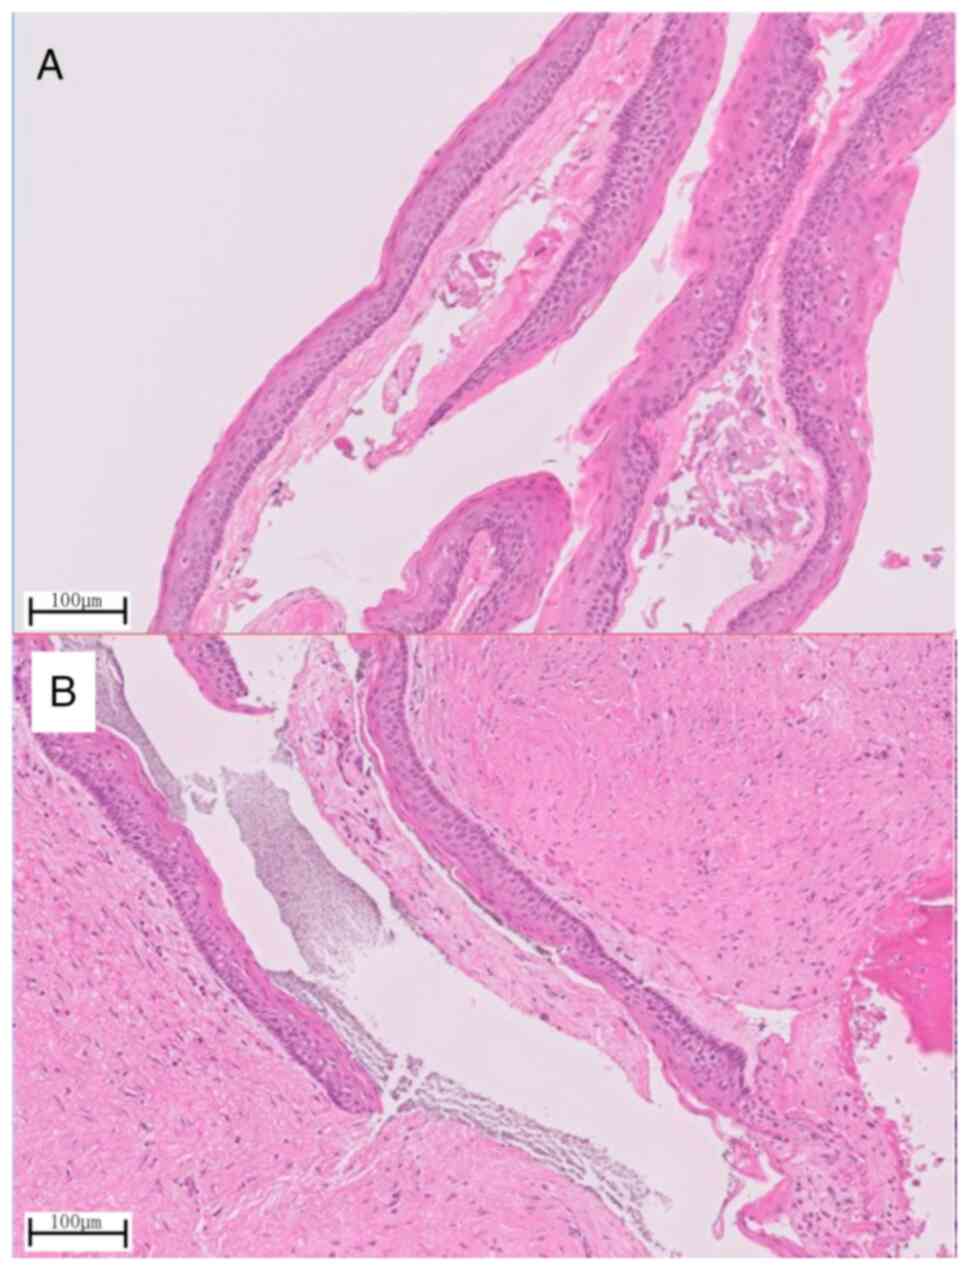

Histopathological examination of the removed

specimen showed cyst walls with a well-ordered squamous epithelial

lining in both the anterior (Fig.

8A) and posterior (Fig. 8B)

cysts. These were typical findings of OKCs showing a palisade

arrangement of basal cells and a wavy structure on the surface.